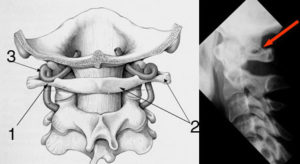

Аномалия Киммерле (или Кимерли) – это порок развития, связанный с изменением формы первого шейного позвонка – атланта. Обычно данное нарушение подразумевает образование в позвонке дополнительной костной дужки, которая нередко сдавливает позвоночную артерию.

Выделяют полный и неполный тип аномалии, что связанно с образованием целостной костной дужки (кольца) или ее части. При этом патология может наблюдаться с одной стороны или иметь двусторонний характер.

Диагноз аномалии Киммерле ставится на основании рентгенограммы черепно-позвоночного перехода в боковой проекции. В некоторых случаях может потребоваться МРТ или КТ.